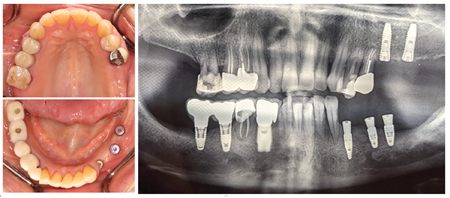

Edentulism in the posterior maxillary region presents a challenging scenario for dental implant rehabilitation due to vertical ridge dimension bone loss and the close proximity to the floor of the maxillary sinus. In addition, alveolar ridge width loss and thinning of mucosa is a common clinical scenario in areas of long term tooth loss. To … Read more